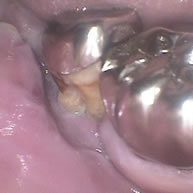

症例2

一番奥の歯が完全に浮いて噛めなくなっています。

左の写真のレントゲンです。奥から 2 番目の歯は動揺がそれほどありませんでしたので、ポケット内の歯石除去を徹底し、根管治療の上保存しました。